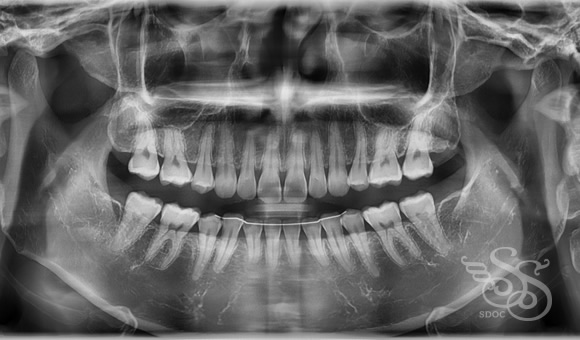

レントゲン:術前